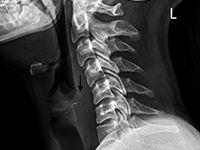

OtherForeign body ingestion is more common in children than in adults, but serious complications are less common in pediatric patients [1, 2]. Among adults, elderly individuals, those with masticatory disorders, esophageal strictures, prisoners, and patients with mental disorders predominate [2-4]. 80-90% of swallowed foreign bodies pass through the upper gastrointestinal tract spontaneously, but 10-20% require endoscopic removal, and 1% cause complications [3,5]. Possible locations of foreign bodies in the midpharynx include the epiglottis, the base of the tongue, the palatine tonsils, and in the hypopharynx, the piriform recesses, the retrocricoid region, and the posterior pharyngeal wall [6, 7]. In the esophagus, foreign bodies are located in the cervical part in over 80% of cases [1, 2, 8]. It is rare for a swallowed foreign body to penetrate the gastrointestinal tract and migrate deep into the soft tissues. This may be facilitated by the foreign body's structure, e.g., sharp-edged pieces of bone or glass. This poses a risk of serious and potentially fatal complications, such as retropharyngeal abscess, mediastinitis, or damage to the large vessels of the neck [7]. In such cases, prompt intervention and removal of the foreign body are essential. We present the case of a patient with a foreign body that migrated from the hypopharynx into the soft tissues of the neck, directly adjacent to the common carotid artery.